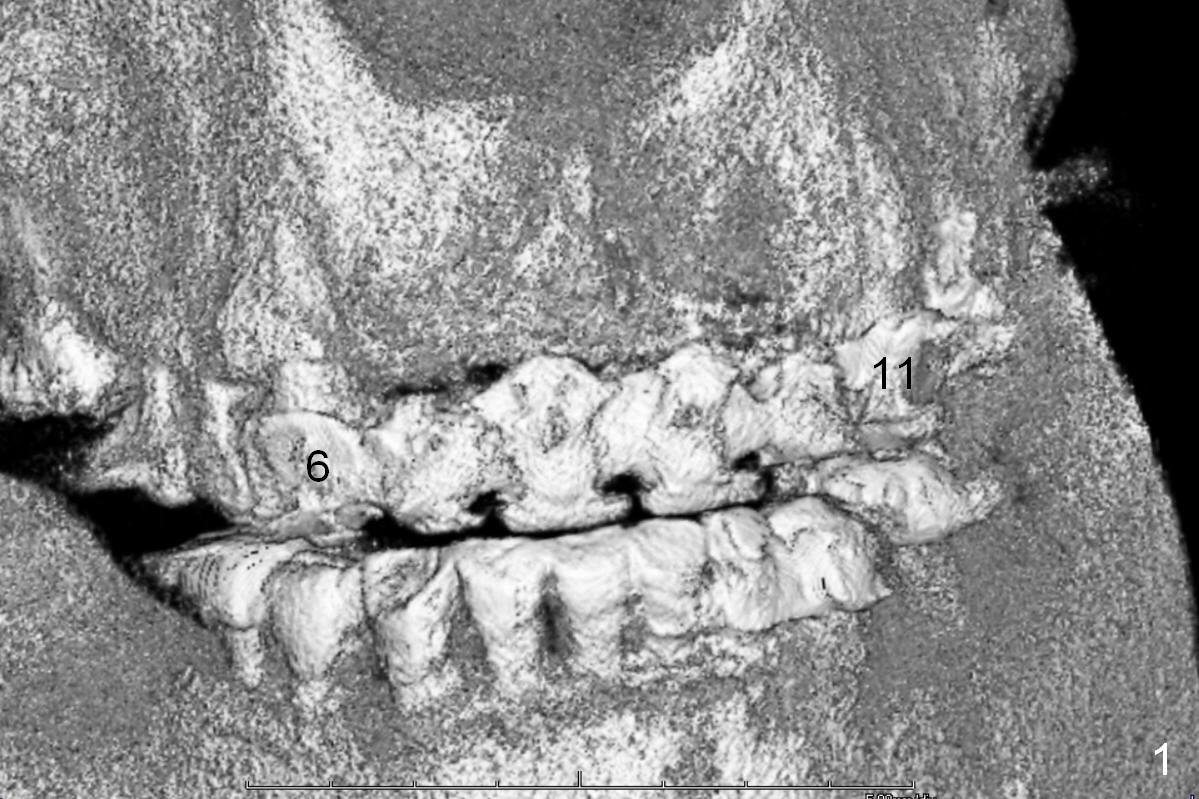

A 60-year-old man is partially edentulous; A 6-unit (#6-10) bridge has been in function for more than 10 years (Fig.1). The connection between #8 and 9 pontics breaks lately. The edentulous ridges are narrow (Fig.2-5), especially at #7 and 10. One piece implants (2.5x14 and 3x14 mm) are planned to be placed at the lateral and central incisor sites, respectively. They should be placed as palatal (P in Fig.2) as possible.